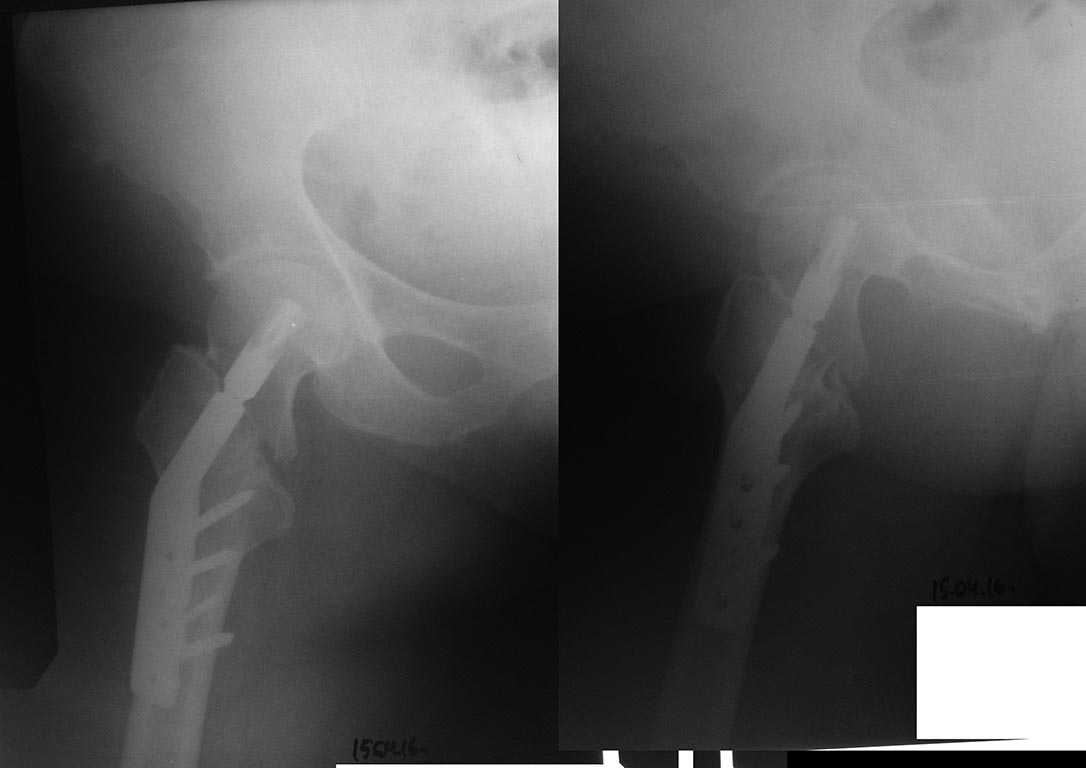

Миграция DHSA при лечение перелома проксимального отдела бедра

Добрый вечер уважаемые коллеги. На консультацию обратилась пациентка 62 лет с жалобами в области правого тазобедренного сустава, хруст и ограничения движения в суставе.

Из анамнеза : 12 апреля 2016 года упала дома на область правого тазобедренного сустава, доставлена в больницу, где больной было наложено скелетное вытяжение, а 14 апреля 2016 года выполнена операция - остеосинтез правого бедра, конструкция DHSA (Китай). Полтора-два месяца находилась в горизонтальном положении, затем вертикализирована, начала передвигаться при помощи ходунков с возрастающей нагрузкой на оперированную конечность.

21 числа больной выполнен рентген контроль, больная отправлена на консультацию к оперирующему хирургу, которым рекомендовано продолжить возрастающую нагрузку и разработку движения в суставе. Больная обратилась вновь ко мне на консультацию. Из анамнеза : около 12 лет нет месячных, около 30 лет проживает в условиях крайнего севера, 3 года принимает бивалос по интересной схеме - по 1 пакетику в течение месяца 1 раз в год, Бонвива по 1 таблетке 1 раз в месяц в течение 2 лет. Страдает двухсторонним Гонартрозом 3 степени. Передвигалась при помощи трости испытывала ограничение движений больше в правом коленном суставе, хромоту.

Прошу рассмотреть несколько вариантов лечения пациентки:

1. Согласиться с рекомендациями оперирующего хирурга (разработка движения и возрастающая нагрузка),

2. Дождаться полной консолидации и удаления винта DHSA,

3. Убрать все в ближайшее время и костная пластика дефекта,

4. Убрать все в ближайшее время + костная АО-пластика + PFNA с аугментацией.